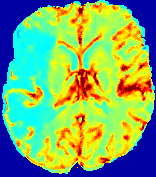

4.3.1 Advection Imaging via Advection-Diffusion

Slice #1Slice #2Slice #3Slice #4Slice #5Slice #6𝐕gt𝟐subscriptnormsuperscript𝐕gt2\|\bf{V}^{\text{gt}}\|_{2}Refer to captionRefer to captionRefer to captionRefer to captionRefer to captionRefer to caption𝐕est𝟐subscriptnormsuperscript𝐕est2\|\bf{V}^{\text{est}}\|_{2}Refer to captionRefer to captionRefer to captionRefer to captionRefer to captionRefer to captionRefer to caption1.51.51.51.21.21.20.90.90.90.60.60.60.30.30.30.00.00.0(mm/s)𝑚𝑚𝑠(mm/s)Destsuperscript𝐷estD^{\text{est}}Refer to captionRefer to captionRefer to captionRefer to captionRefer to captionRefer to captionRefer to caption0.0150.0150.0150.0120.0120.0120.0090.0090.0090.0060.0060.0060.0030.0030.0030.0000.0000.000(mm2/s)𝑚superscript𝑚2𝑠(mm^{2}/s)

Figure 14: PIANO identifiability testing: advection imaging via advection-diffusion. Top row shows 𝐕gt2subscriptnormsuperscript𝐕gt2\|{\bf{V}}^{\text{gt}}\|_{2} used for simulating ground truth pure advection. Rows below show the estimated 𝐕est2subscriptnormsuperscript𝐕est2\|{\bf{V}}^{\text{est}}\|_{2} and Destsuperscript𝐷estD^{\text{est}} on corresponding slices. Note that the plotted value scale for Destsuperscript𝐷estD^{\text{est}} is 0.01 of that for 𝐕gt2subscriptnormsuperscript𝐕gt2\|{\bf{V}}^{\text{gt}}\|_{2} and 𝐕est2subscriptnormsuperscript𝐕est2\|{\bf{V}}^{\text{est}}\|_{2}.

We use the same ‘Advection Imaging’ simulation of Sec. 4.2.1 as the concentration dataset for PIANO. However, instead of modeling pure advection (Eq. 15), we let PIANO estimate both velocity 𝐕estsuperscript𝐕est{\bf{V}}^{\text{est}} and diffusivity Destsuperscript𝐷estD^{\text{est}} via the advection-diffusion PDE (Eq. 2) underlying the proposed PIANO model. Fig. 14 shows the estimated 𝐕est2,subscriptnormsuperscript𝐕est2\|{\bf{V}}^{\text{est}}\|_{2}, and Destsuperscript𝐷estD^{\text{est}} fields for one patient. Although PIANO has the freedom to estimate both a velocity and a diffusivity field from pure advection, PIANO differentiates well between advection and diffusion: the estimated 𝐕est2subscriptnormsuperscript𝐕est2\|{\bf{V}}^{\text{est}}\|_{2} successfully reproduces the ground truth 𝐕gt2subscriptnormsuperscript𝐕gt2\|{\bf{V}}^{\text{gt}}\|_{2} governing the simulated advection process, just as it already did in the ‘Advection Imaging via Advection’ test (Fig. 12). More importantly, the estimated diffusivity Destsuperscript𝐷estD^{\text{est}} is orders of magnitudes smaller than 𝐕est2subscriptnormsuperscript𝐕est2\|{\bf{V}}^{\text{est}}\|_{2}, indicating the estimated diffusion is negligible compared to the estimated advection, which is highly consistent with the underlying pure advection of the simulated data.